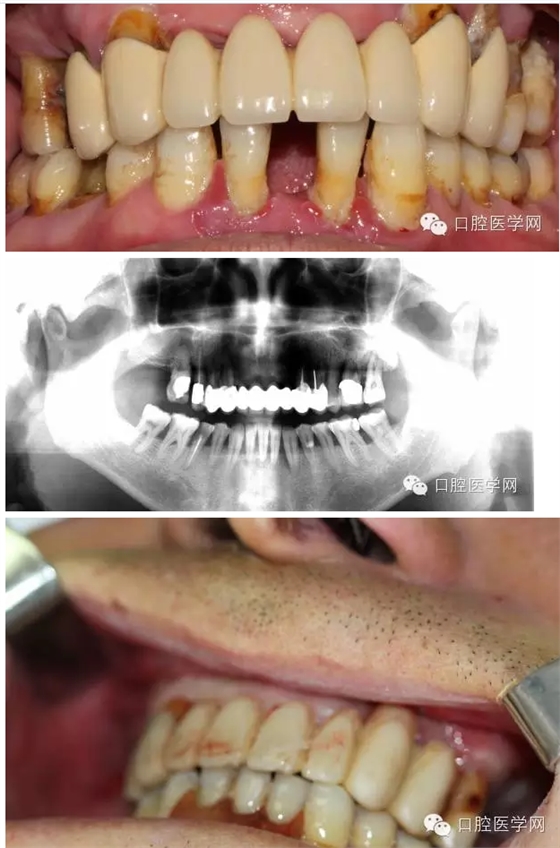

患者情況

男,61歲,無過敏史

主訴:全口牙咬物無力來就診

現(xiàn)病史:一年來全口牙吃東西沒力氣,牙齒松動現(xiàn)要求治療

檢查:11、12、17、21、22、26缺 14到25 固定橋,且松動,且牙齦紅腫稍溢膿 15 26單冠,松動3度 16 27殘冠2度松動 42到32 缺一顆臨時活動義齒修復(fù) 42到32松動3度(+) 牙槽骨吸收超過根長三分之二無法保留35 36 45 46 殘冠 冷診痛 (45為根管治療后沒有修復(fù))其與牙不同程度松度 牙結(jié)石 牙齦紅腫。

初步診斷:1上頜不良修復(fù)體;2牙周炎;3 35 36 45 46牙髓炎